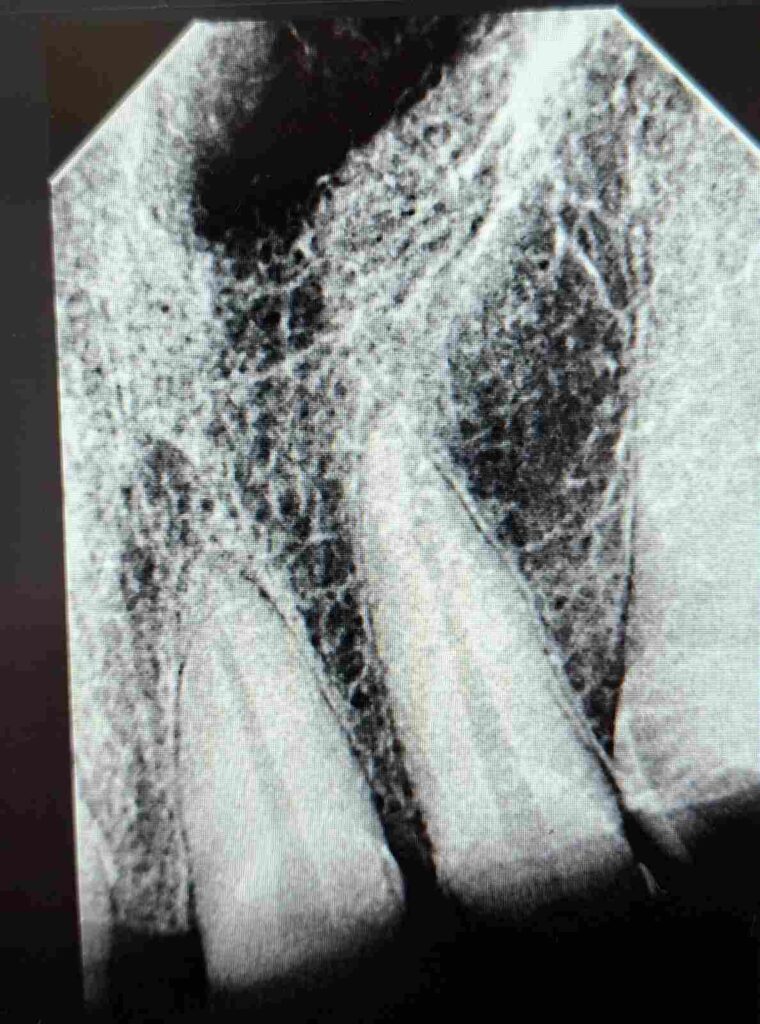

Tras la evaluación clínica y radiográfica detallada, se indicó tratamiento endodóntico en los dientes 11, 12, 21 y 22 con el objetivo de restablecer la salud del sistema de conductos radiculares y crear una base biológica sólida para la posterior rehabilitación protésica del sector anterior.

Durante todo el protocolo se realizaron irrigaciones activas con soluciones desinfectantes, garantizando la eliminación completa de detritos y microorganismos. Finalmente, se completó la obturación tridimensional del sistema radicular, logrando un sellado hermético confirmado por control radiográfico.